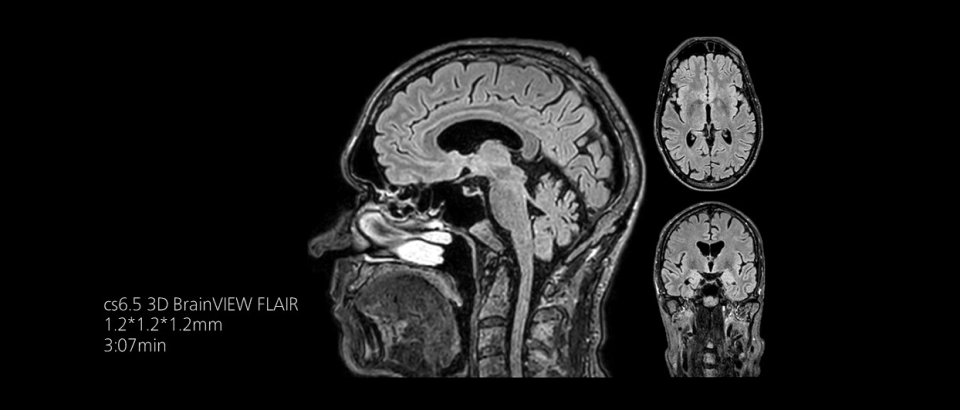

時間を味方につける - Compressed SENSEを使用すると、実質的に同等の画質を保ちつつ、撮像時間を最大50%²短縮できます。空間分解能が60%向上した高品質のMR画像を得ることで確実な診断が可能になります。